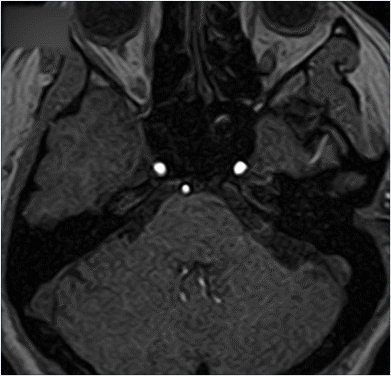

因此,在日常体检过程中,我们要尤其注意脑动脉瘤的筛查。上文中,医生给“龙妈”检查脑动脉瘤时,使用MRI无创无辐射检查,就可以清晰地看清脑部血管的病变。

磁共振扫描是无创无辐射的绿色检查,可以用来做脑部血管成像,在动脉瘤破裂之前,尽早发现,尽早治疗。

作为国产磁共振第一品牌,朗润医疗磁共振配有100秒MRA脑动脉瘤筛查技术,无需造影剂即可准确识别血管,清晰筛查血管3mm动脉瘤,让脑动脉瘤无处遁形。

在脑部血管检查方面,朗润医疗磁共振使用压缩感知成像,可以实现100秒快速成像,在最快时间内让患者确诊,最大限度地争取治疗的“黄金时间”。